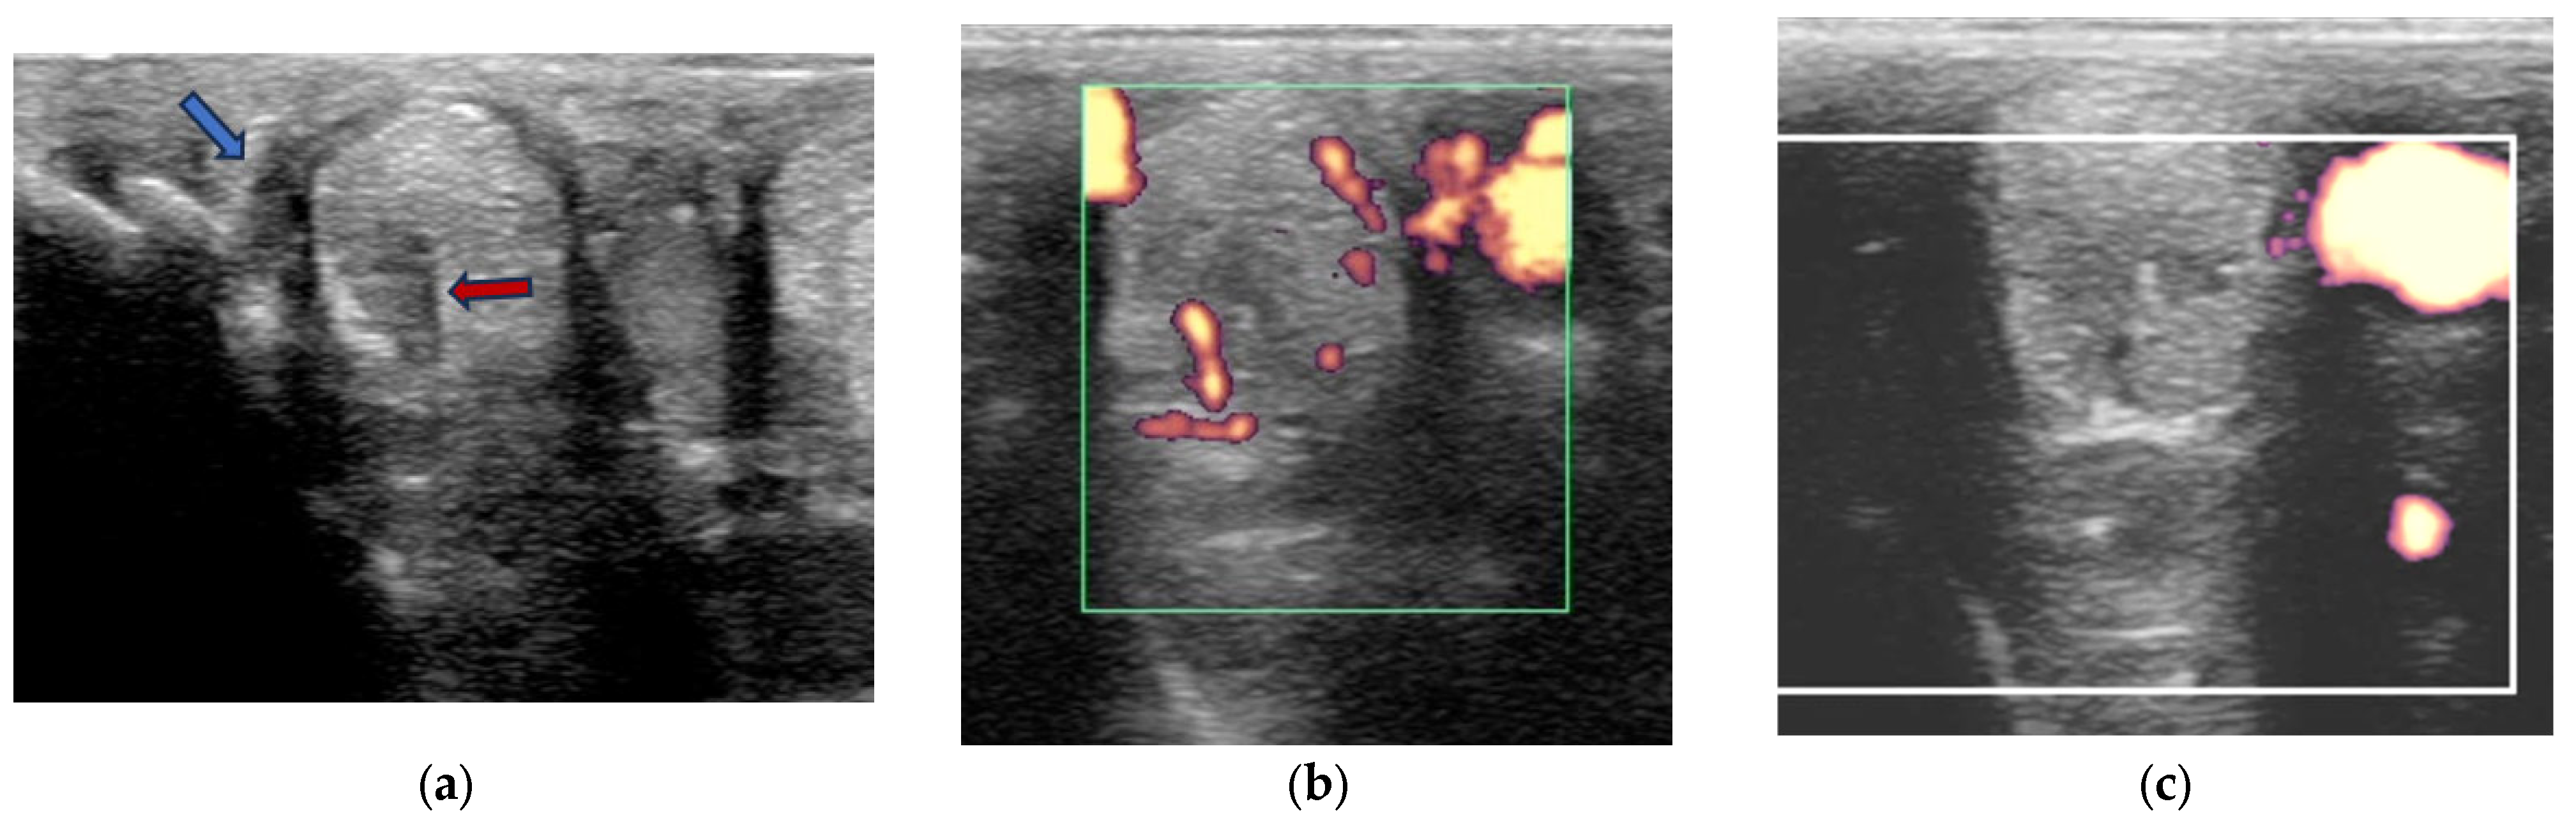

Power Doppler examination was performed in 62/89 branches (67.4%). Doppler signal was present in 59/62 (95.2%) branches (Figure 5, Figure 6, Figure 7 and Figure 8) and absent in three branches. At the initial examination, Doppler signal was classified as mild in 22/62 branches (35.5%), moderate in 25/62 (40.3%) and severe in 12/62 (19.4%) branches. Doppler signals persisted in follow-up examinations, despite treatment, in 17/62 branches (27.4%) (Figure 7).

Figure 5. Twelve-year-old Warmblood mare; (a) B-mode transverse ultrasonographic image of the left forelimb lateral suspensory branch five days after injury. There is a well-defined hypoechoic region (red arrow) within the branch, and a hypoechoic region subcutaneously consistent with periligamentous oedema (blue arrow); (b) power Doppler image at the same level as (a). There is severe power Doppler signal. (c) Transverse power Doppler image one month after injury; there is no periligamentous oedema, the lesion in the branch is less well-defined and there is no power Doppler signal within the branch.